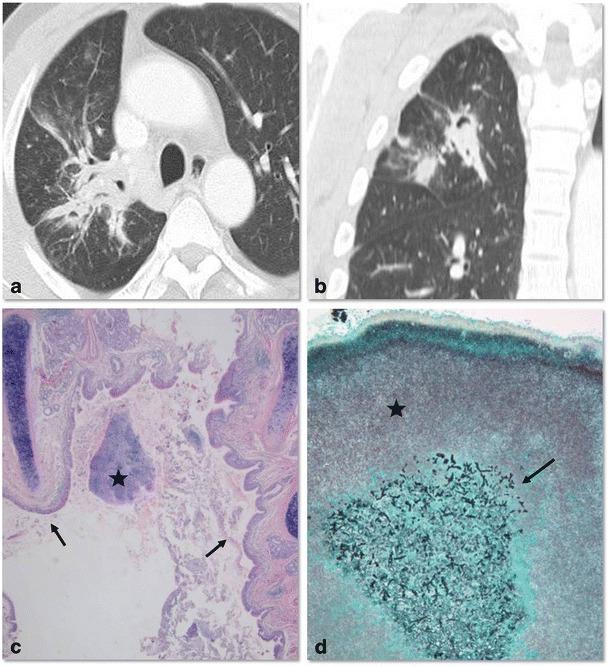

Thoracic actinomycosis can be radiologically divided into the parenchymal type, the airway type including bronchiectasis, the endobronchial form, and the mediastinum or chest wall involvement type.

• Important risk factors for thoracic actinomycosis are underlying respiratory disorders such as emphysema and chronic bronchitis. • Different CT patterns can be distinguished in thoracic actinomycosis: parenchymal, bronchiectatic, endobronchial and extrapulmonary. • Typical CT findings in the parenchymal pattern are a central low density within the parenchymal consolidation and adjacent pleural thickening.

胸放线菌病可在放射学上分为实质型、气道型(包括支气管扩张)、支气管内型和纵隔或胸壁受累型。

• 胸放线菌病可区分不同的 CT 模式:实质型、支气管扩张型、支气管内型和肺外型。

• 实质型的典型 CT 表现为实质浸润内的中央低密度影和相邻胸膜增厚。